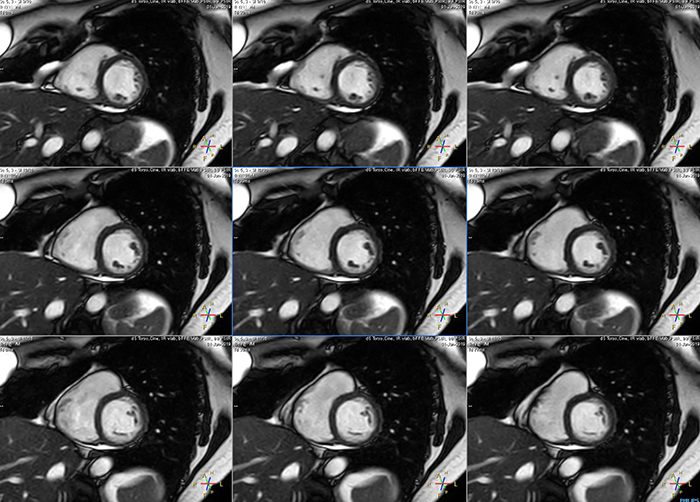

Short breath hold cardiac cine

MCVI Ambition Short breath hold cardiac cine

These are some images of a cardiac cine scan with a short breath-hold time. A high temporal resolution provides a smooth cine, which helps in assessing heart function. Ingenia Ambition.

Avila says that Compressed SENSE allows them to reduce breathhold time to 3 to 4 seconds in cardiac cine scans. “At the same time, we can now – based on cardiac frequency – obtain as many as 30 to 40 cardiac phases without sacrificing resolution, while before Ingenia Ambition, we were acquiring only 20 phases.

“This ability to use Compressed SENSE for obtaining higher temporal resolution translates to a much smoother cine. This allows me to better assess heart function,” Dr. Peña says.